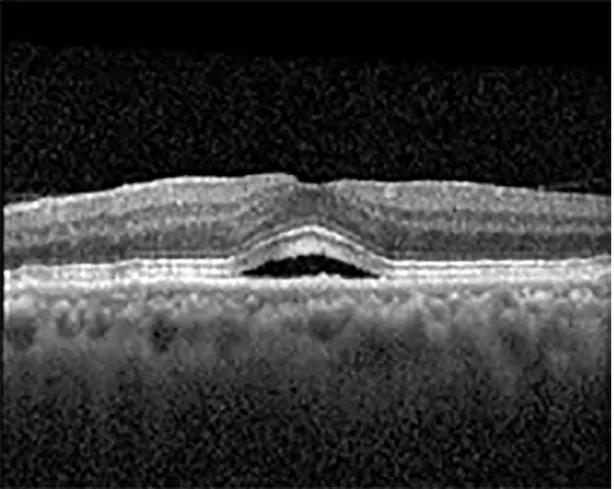

The patient began treatment with oral pemigatinib daily and was followed up for an ophthalmic examination during the second treatment cycle approximately 5 weeks into the treatment process. The patient had at this stage received 28 doses of 13.5 mg per day, which was administered in cycles of 14 on-days and 7 off-days, and had no visual or ophthalmic complaints. The non-corrected VA was OD 20/30 + 1 and OS 20/20. The OCT examinations revealed subfoveal SRF bilaterally. The fundus examination was otherwise unremarkable outside the patient’s prior documented peripheral drusen. Repeat autofluorescence was overall unchanged, though a slight hypofluorescent ring may be visualized in Figure 2. The current pemigatinib protocol recommendation for asymptomatic patients suggests no dose modification; however, with worsening presentation or positive symptoms, it is recommended to withhold pemigatinib. After discussion with the patient’s oncologist, it was decided to continue the medication at this time. Serial monitoring of the patient’s symptoms, vision, and SRF were conducted on specific days during active treatment cycles and days off-cycle to monitor the SRF. Subsequent evaluations demonstrated complete resolution of SRF while off-cycle, and asymptomatic re-accumulation of fluid while on-cycle with varying levels of VA. (Table 1) As we see demonstrated in the table below, in the later stages of the active cycles, such as day 13 of 14 of cycle 2, day 13 of 14 of cycle 3, day 13 of 14 of cycle 4, and day 14 of 14 on cycle 5, the patient’s VA showed no correlative changes based on the presence of SRF. The fluctuations in the patient’s VA certainly occurred, but were likely to be secondary to surface changes, as certain off-cycle days actually presented with lower acuities than days when the SRF was present on OCT examination.

| Cycle, day, on/off | VA OD; OS | CMT OD; OS | OCT OD | OCT OS |

| Cycle 2, day 4, off | 20/30−2; 20/20−2 | 282; 280 | ![]() | ![]() |

| Cycle 3, day 6/14, on | 20/40−1; 20/30−1 | 306; 301 | ![]() | ![]() |

Highlights the visual acuity, central macular thickness, and the physical OCT of the macula for this patient in both the right and left eyes during various stages of the patient's chemotherapy treatment cycle.